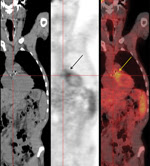

Figure. Positron emission tomography/computed tomography fusion imaging for a 56-year-old man in southern France with Bartonella henselae prosthetic valve endocarditisLeft panel, frontal computed tomography image showing morphologic findingsMiddle panel, 18F-fluorodeoxyglucose positron emission...

An 18FDG-PET/CT scan was performed and showed 18FDG uptake in the aortic bioprosthesis area (Figure). Results of a whole body scan were normal. An immunofluorescence test for Bartonella spp. showed titers of 400 for IgG against B. quintana and B. henselae (1), and Western blot confirmed a reactivity pattern pathognomonic for B. henselae endocarditis. Results of a PCR performed with a blood sample stored in EDTA (1) were positive for B. henselae. On day 13, antimicrobial drug therapy was changed to oral doxycycline, 200 mg/day for 1 month and intravenous gentamicin, 160 mg/day for 15 days. On day 28, the patient was released from the hospital.